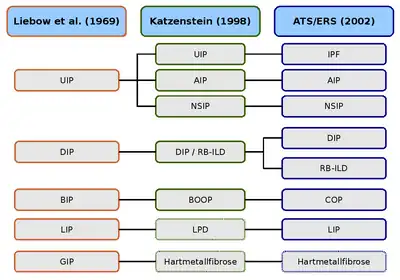

UIP : pneumonie interstitielle usuelle — IPF : Fibrose pulmonaire idiopathique — AIP : Pneumonie interstitielle aigüe — NSIP : Pneumonie interstitielle non spécifique

DIP : Pneumonie interstitielle desquamative — RB-ILD : Bronchiolite respiratoire avec maladie pulmonaire interstitielle

BIP : Pneumonie interstitielle bronchiolitique — BOOP : Bronchiolite oblitérante avec pneumonie organisante — COP : Pneumonie interstitielle cryptogène

LIP : Pneumonie interstitielle lymphoïde — LPD : Maladies lymphoprolifératives

GIP : Pneumonie à cellules géantes — Hartmetallfibrose : Fibrose des métaux durs.

Historique

La première description d'une maladie interstitielle remonte à 1892, et vient du médecin canadien William Osler. Il a déjà reconnu la multiplicité des manifestations cliniques, et attira l'attention sur la nécessité, et la difficulté, d'une classification plus fine de ces maladies.

L'interniste Louis Virgil Hamman et le pathologiste Arnold Rice Rich ont décrit en 1944 quatre cas de patients atteints d'une fibrose interstitielle diffuse. On nomma ce tableau clinique syndrome de Hamman-Rich. Ce concept a été ensuite un certain temps utilisé pour toutes les maladies où survenait une fibrose diffuse du poumon d'origine inconnue, bien qu'il s'agisse dans les cas décrits d'évolutions aigües. Probablement, les auteurs ont décrit ce qui correspond actuellement à une pneumopathie interstitielle aiguë.

La première classification histologique des pneumopathies interstitielles diffuses idiopathiques est due aux deux pathologistes Averill Abraham Liebow et Charles B. Carrington (1969). La classification d'alors distinguait cinq types histologiques, qui ont été rassemblés sous le concept global de pneumopathies interstitielles diffuses idiopathiques. Le syndrome de Hamman-Rich a été rangé comme variante aigüe de la pneumonie interstitielle usuelle. En 1997, la classification de Liebow-Carrington a été développée en 1997 parAnna-Luise A. Katzenstein, puis en 1998 en collaboration avec Jeffrey L. Myers, et ajustée à l’état actuel de la recherche. La cause de la pneumonie à cellules géantes a été entretemps trouvée. Elle est déclenchée par l'inhalation de poussières métalliques, et maintenant désignée comme fibrose des métaux durs. La pneumonie interstitielle lymphoïde a été rangée dans les maladies lymphoprolifératives[36],[37]